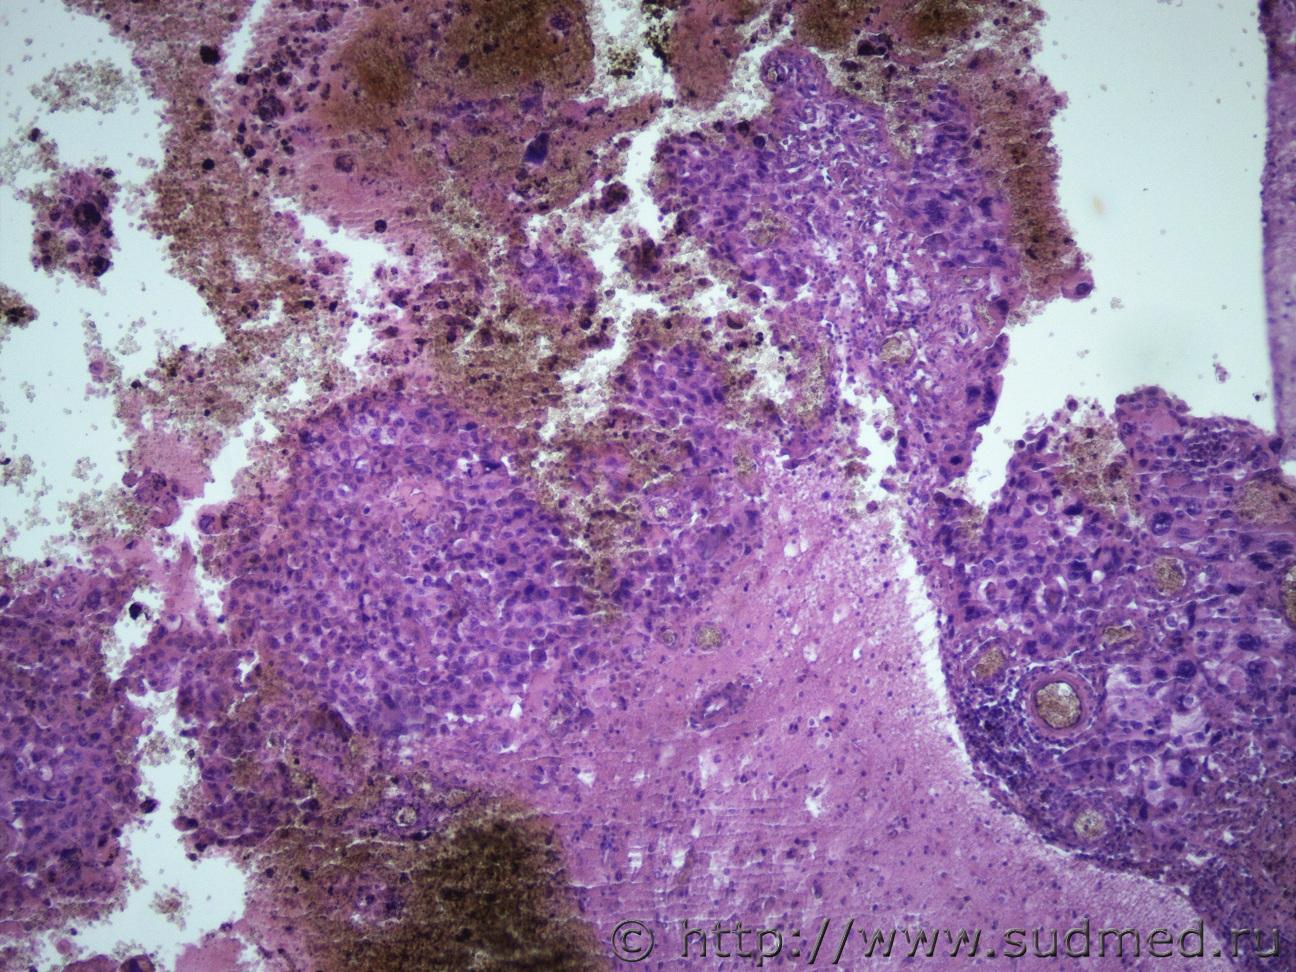

Ув. коллеги, сегодня в рубрике опухоль головного мозга. Муж 60 лет в лобной и теменной доле макро образования с кровоизлияниями; микро опухолевый рост под мягкой мозговой оболочкой и в толще вещества головного мозга. Судебная медицина - Прикрепленное изображение Судебная медицина - Прикрепленное изображениеСудебная медицина - Прикрепленное изображениеСудебная медицина - Прикрепленное изображениеСудебная медицина - Прикрепленное изображение

Какая злючка. Олигодендро... Без подсказки не разберу.

Наверное,это глиобластома.

Я тоже склоняюся к глиобластоме. Но так как видела ее всего один раз за время работы, чувствую не уверенность в себе)))). Спасибо всем участвующим в моих темах. Закидываю вас ими не ради развлечения, а накопления опыта.